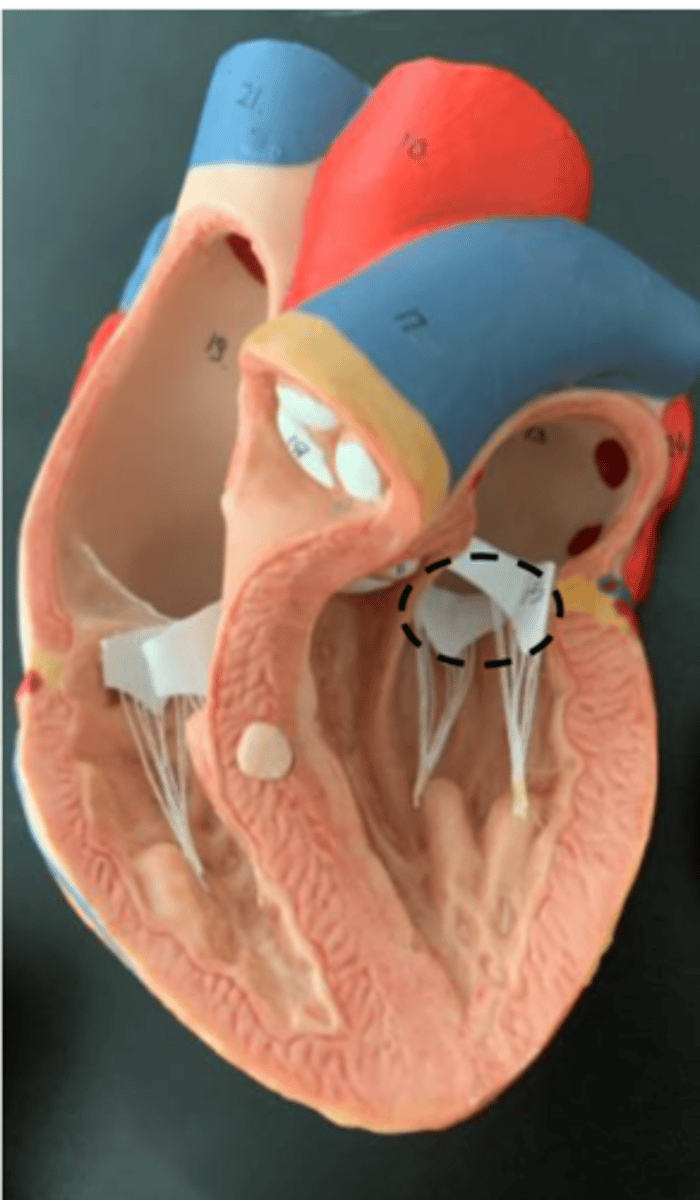

tricuspid valve

AKA: right atrioventricular valve, (Found on top of the chordae tendineae)

<p>AKA: right atrioventricular valve, (Found on top of the chordae tendineae)</p>

chordae tendineae

the little strings below the tricuspid and bicuspid valve

<p>the little strings below the tricuspid and bicuspid valve</p>